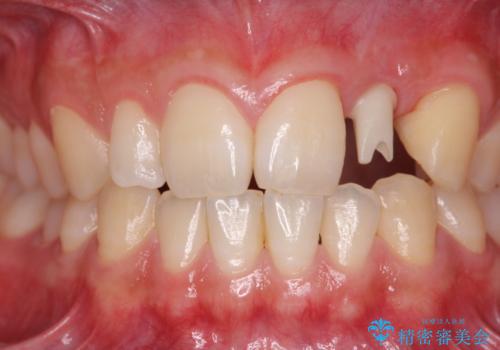

- 前歯の永久歯が元々なく、乳歯を失ったタイミングで前歯の審美性の回復を求めて来院されました。

機能・審美性の回復手段として、インプラント治療・ブリッジ・部分床義歯が考えられます。

それぞれの治療に特徴がありますが、取り外しの必要がなく隣の歯を削る必要も必要ないインプラント治療を選択されました。

前歯部にインプラントを埋入し、きれいに仕上げるためには骨の造成技術や歯肉の厚みを増すような処置を行い、インプラント周囲の環境を整備することが肝要です。